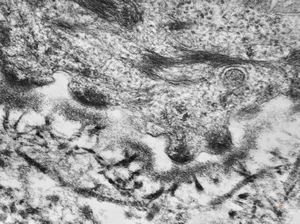

oral saprophytic bacterium